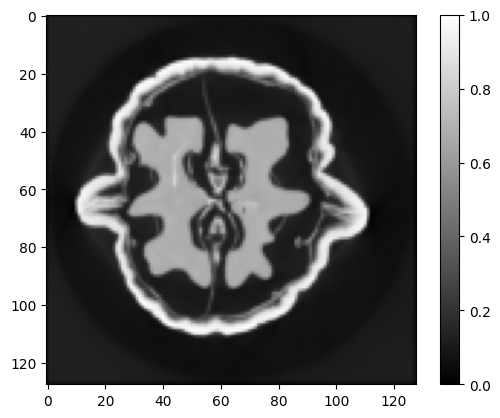

Refer to caption

(a) Gibbs-BPS

(b) PLD

Figure 9: Comparison of CT reconstruction for Lung CT Image 1 with fused L1/2L_{1/2} prior and fused LASSO prior. The upper images are posterior mean. The bottom images are posterior standard deviations.

Table 4 and Figure 7 compare the convergence speed of MCMC algorithms for large-scale images. We see that when dealing with high-resolution images, the advantages of Gibbs-BPS become evident. It is the most efficient for Walnut Phantom with 128×128128\times 128 pixel, then followed by Gibbs sampler and PLD. The pCN has the slowest convergence speed. For two lung CT images with 256×256256\times 256 pixel, the Gibbs sampler does not work due to the inability to sample the Gaussian distribution with dimensions 2562256^{2}, and we also found that the pCN suffers from numerical instability. The proximal Langevin dynamic is the only competitor for the problem with size. In this case, the Gibbs-BPS converges slightly faster than PLD. Figures 8-10 show the posterior statistics for the three high resolution images recovered by various methods. For Walnut Phantom, the image recovered by all the methods except for edge-preserving horseshoe prior have the similar quality. For two lung CT images, the fused L1/2L_{1/2} prior always did slightly better than the fused LASSO prior in terms of PSNR. The posterior standard deviation estimated by the PLD algorithm is much smaller than Gibbs-BPS. Since this phenomenon consistently holds for all the scenarios for PLD, we suspect that the PLD may underestimate the posterior standard deviations.